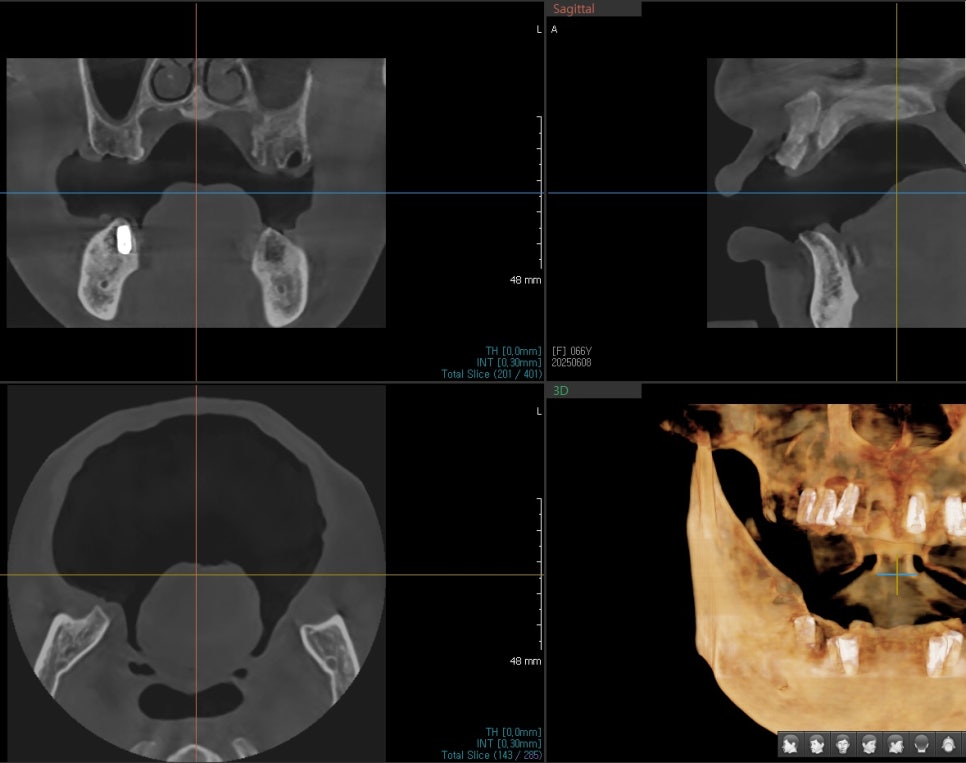

Detailed Diagnosis and Treatment Plan

At Seoulove Dental Hospital, we first performed a detailed 3D CT analysis of the entire upper and lower jaws,

then established the treatment plan.

- Placement of a total of 13 implants in the upper and lower jaws

- Bone grafting with allograft material where bone was insufficient

- Bite design centered on the molars

- Final prosthetics custom-made in our in-house lab